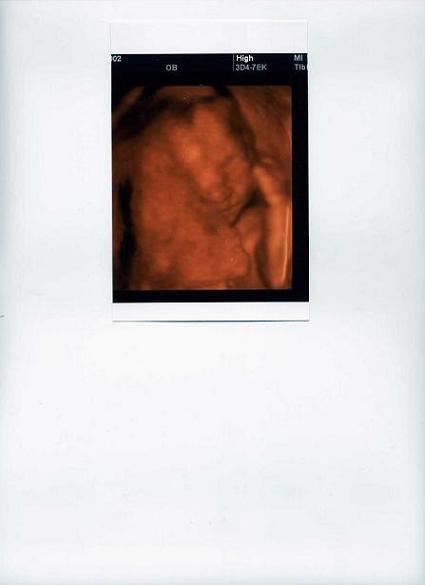

zuzmi örülök, hogy kisfiatok lesz! örülök, hogy minden rendben van a vele, nagyon cuki kis krapek.

az én lepényem is elöl fent tapad, és az én kicsikém is az arca elé pakolta a kezeit meg lábait.

remélem a 4 D-n jó kislány lesz.